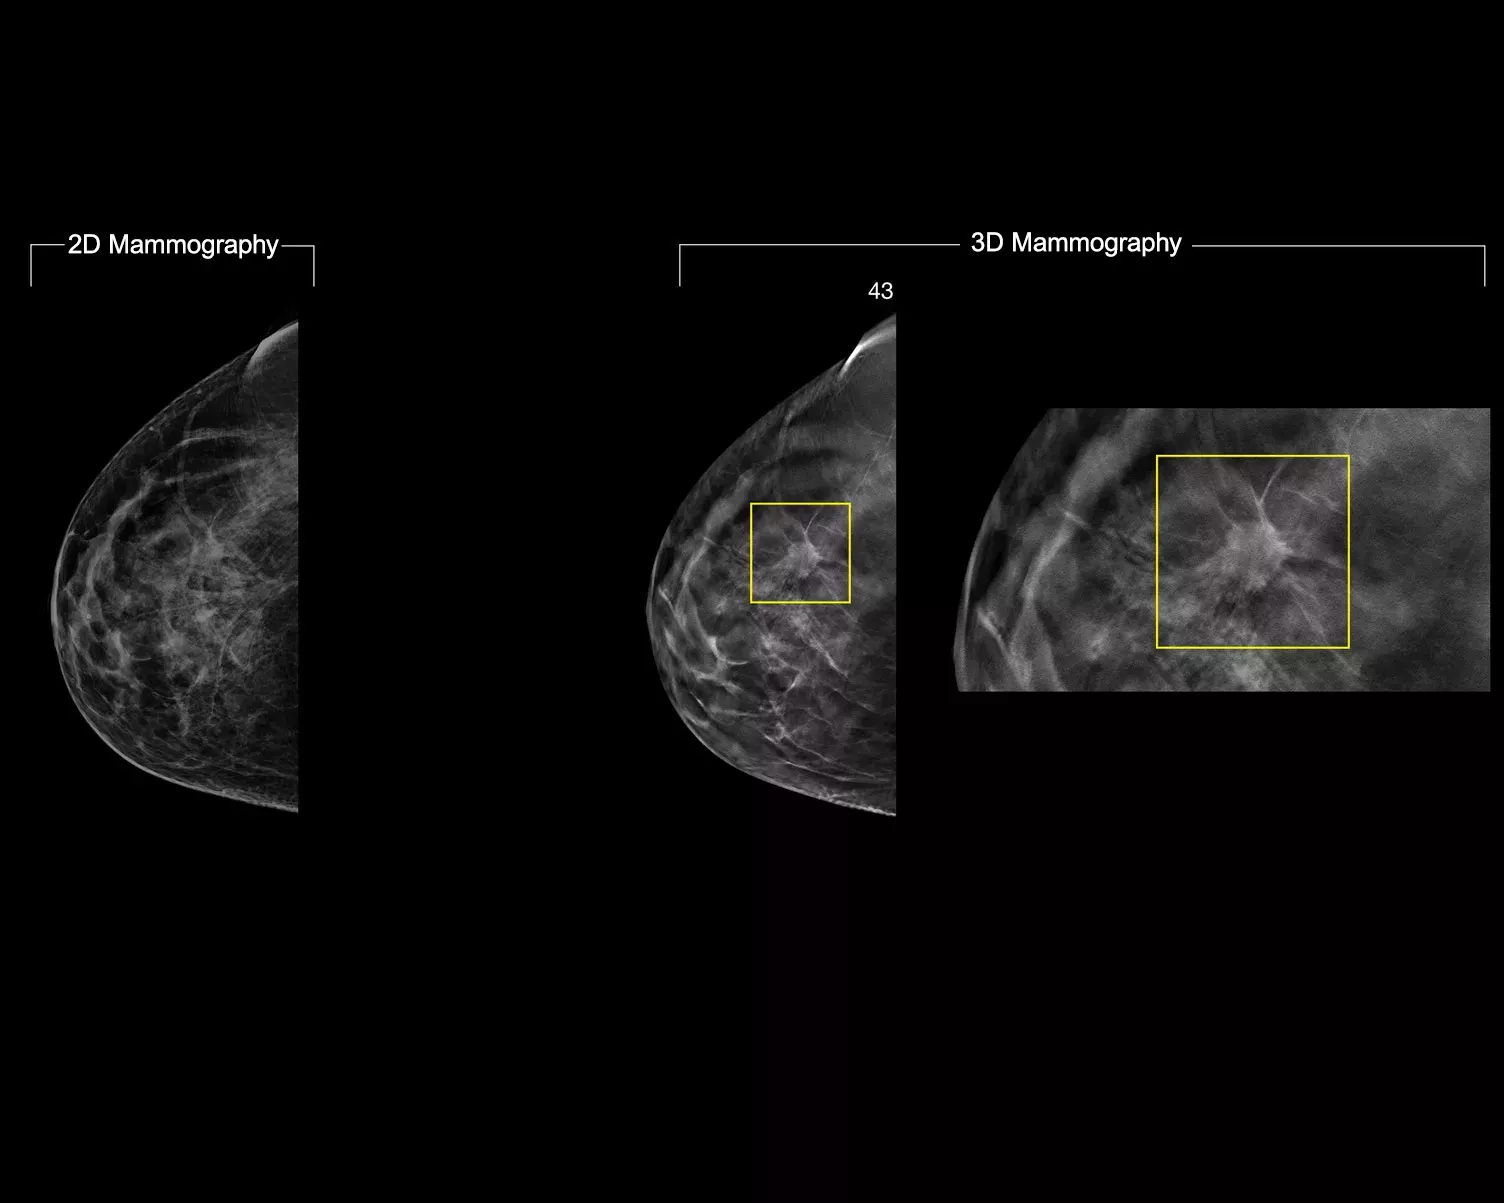

Enquanto os exames 3D Mammography permitem um desempenho médico superior comparativamente com a mamografia 2D isoladamente,1-4 alguns radiologistas desejam mais: melhor qualidade de imagem, ver mais detalhes, melhores tempos de leitura e menores níveis de radiação.

Preserve mais características de interesse graças aos dados de mamografia 3D de alta resolução. Utilize a análise com base em IA para visualizar com confiança características do tecido subtis e lesões nas imagens 2D sintetizadas e reconstruídas.

Acelere os tempos de leitura do exame de mamografia 3D graças à funcionalidade de mapeamento integrada do Intelligent 2D, comparativamente à mamografia 2D.

• Contraste de imagem 2D excecional com uma representação semelhante à FFDM do tecido parenquimático com uma resolução de 70 μm.

• Desloque-se de áreas suspeitas detetadas na imagem 2D para o ponto de interesse na lâmina da mamografia 3D.